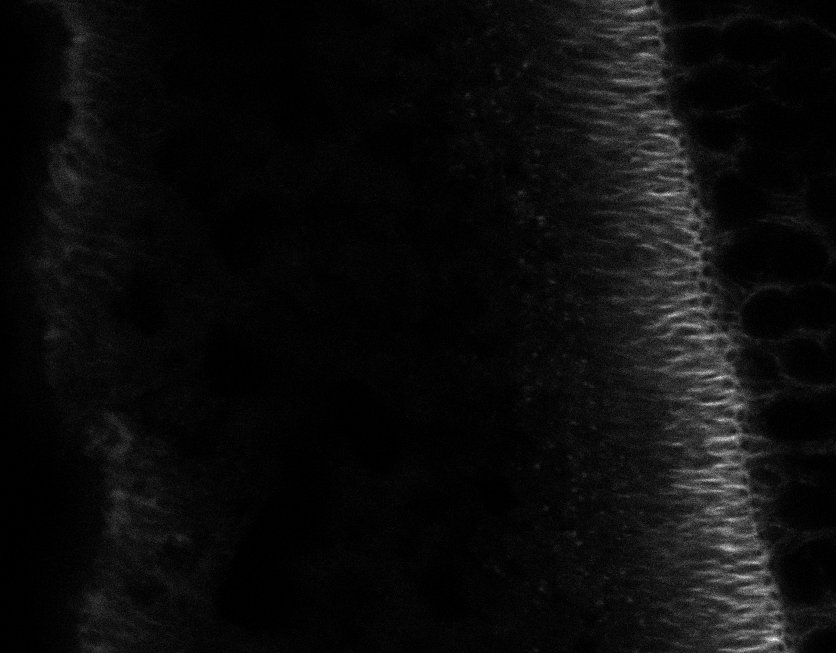

Tubulin

Tubulin - Bip

Tubulin - Nuc